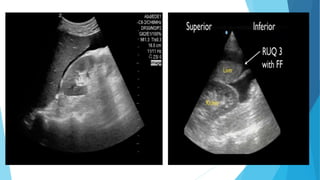

Ultrasonography

 The focused abdominal sonography for trauma (FAST) emerged

recently as an important tool in the initial diagnosis of intra-

abdominal injuries.

 Performed by surgeons or emergency room physicians, FAST has

shown an excellent sensitivity in identifying intra-abdominal fluid.

 Because of its ease of use, repeatability, and avoidance of radiation

exposure it has rapidly become an essential part of the initial

evaluation.

 In the presence of multiple Intraperitoneal injuries, blood is most

often found by FAST in the right upper quadrant.

 At this point, it seems that the most significant contribution of the

FAST examination is in the detection of intra-abdominal fluid in the

hemodynamically unstable and clinically unevaluable blunt trauma

victim.

 These patients should be immediately taken to the operating room for

abdominal exploration.

 Negative FAST exams do not preclude the need for further evaluation of

the abdomen by other imaging modalities, most commonly computed

tomography (CT).

 FAST

Positive or negative????

Treatment. Explain

Case 1

 Positive or negative???

 Next Step in the management????